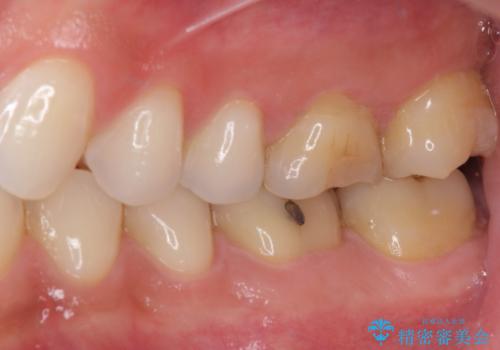

ゴールドインレーは銀歯のインレーやセラミックインレーと比べ、「技工操作の精度が高く、適合が著しく良い」というメリットがあります。特に上の奥歯は歯科医師の操作が行いにくいため、「適合の良さ」は再治療のリスクを防ぐ上でとても重要な要素となります。

上の奥歯は金属色が見えることもないため、審美的な問題は全くありません。